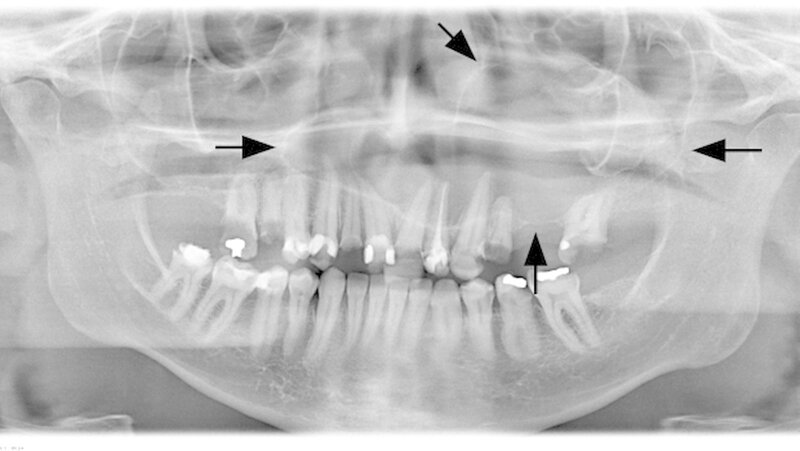

Der intraorale Zahnstatus beschreibt einen insgesamt sanierungsbedürftigen Zustand mit diversen nicht erhaltungswürdigen Zähnen im Unter- und Oberkiefer. Der Oberkiefer zeigte klinisch im zweiten Quadranten eine ausgeprägte palatinale Schwellung (Abbildung 2). Die Panoramaschichtaufnahme bestätigte den klinischen Verdacht auf eine ausgedehnte osteolytische Raumforderung im Oberkiefer. Diese erstreckte sich vom linken Oberkiefer die Mittellinie überschreitend, die gesamte linke Kieferhöhle einnehmend bis zur Regio 14 gehend (Abbildung 3). Durch den Hauszahnarzt konnte ein sechs Jahre zuvor erstellter Zahnfilm zur weiteren Diagnostik hinzugezogen werden.

Bereits damals wurde vom Hauszahnarzt eine Entfernung der noch umschriebenen Raumforderung dringend empfohlen. Der Zahnfilm zeigte ein zystisches Geschehen in der Regio 24 und 25 (Abbildung 4). Zur aktuellen weiteren präoperativen Diagnostik wurde eine Computertomografie angefertigt. In den coronalen Schnitten ist die die Mittellinien überschreitende Raumforderung bis zum knöchernen Nasenboden unter Einbezug der linken Kieferhöhle deutlich zu sehen (Abbildung 5a). Man erkennt insbesondere in den sagittalen Schnitten, dass die Raumforderung über zwei Drittel der linken Kieferhöhle beansprucht (Abbildung 5b).

In diesem Falle erscheint aufgrund des vorliegenden Zahnfilms und der schon hier erkennbaren osteolytischen Veränderung mit direkter Beziehung zu einem endodontisch behandelten Zahn eine radikuläre Zyste als Verdachtsdiagnose naheliegend. Zudem weist das eher verdrängende Wachstum ohne Destruktion oder infiltrierendes Wachstum auf eine benigne Dignität hin. Als weiterer Anhaltspunkt für die Diagnosefindung kann die Konvexität einer Osteolyse herangezogen werden. Eine von der Radix des Zahns ausgehende konvexe Osteolyse, die trichterförmig in den Parodontalspalt übergeht, spricht eher für eine radikuläre Zyste, wohingegen eine konkave Osteolyse - mit eventueller Anresorption der Zahnwurzel - auf eine neoplastische Veränderung verweist.